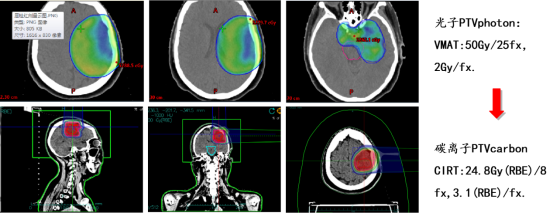

Treatment plan: Combined photon and carbon ion therapy (CIRT):

Carbon ion radiotherapy (CIRT) for the treatment of gliomas began in the 1990s. The advent of CIRT has provided a new option for patients with high-grade gliomas, particularly those with recurrent high-grade gliomas. A clinical study on CIRT boost for high-grade gliomas included 48 patients who underwent surgical treatment, nimustine chemotherapy, and conventional photon radiotherapy (50 Gy/25 fractions), followed by a CIRT boost. Based on the CIRT dose, patients were divided into three groups: low-dose (16.8 Gy (RBE)), medium-dose (18.4–22.4 Gy (RBE)), and high-dose (24.8 Gy (RBE)). The median overall survival (mOS) for the three groups was 7, 19, and 26 months, respectively, with no severe acute or chronic adverse effects reported. Univariate analysis showed that higher CIRT doses were associated with better outcomes.